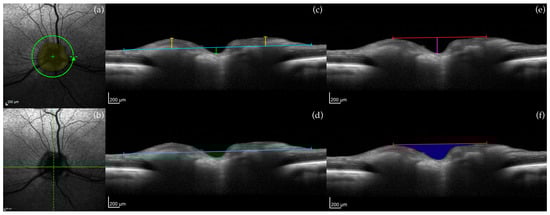

2.3.1. Optic Nerve Head (ONH) Measurements

2.3.2. Retinal Layer Measurements